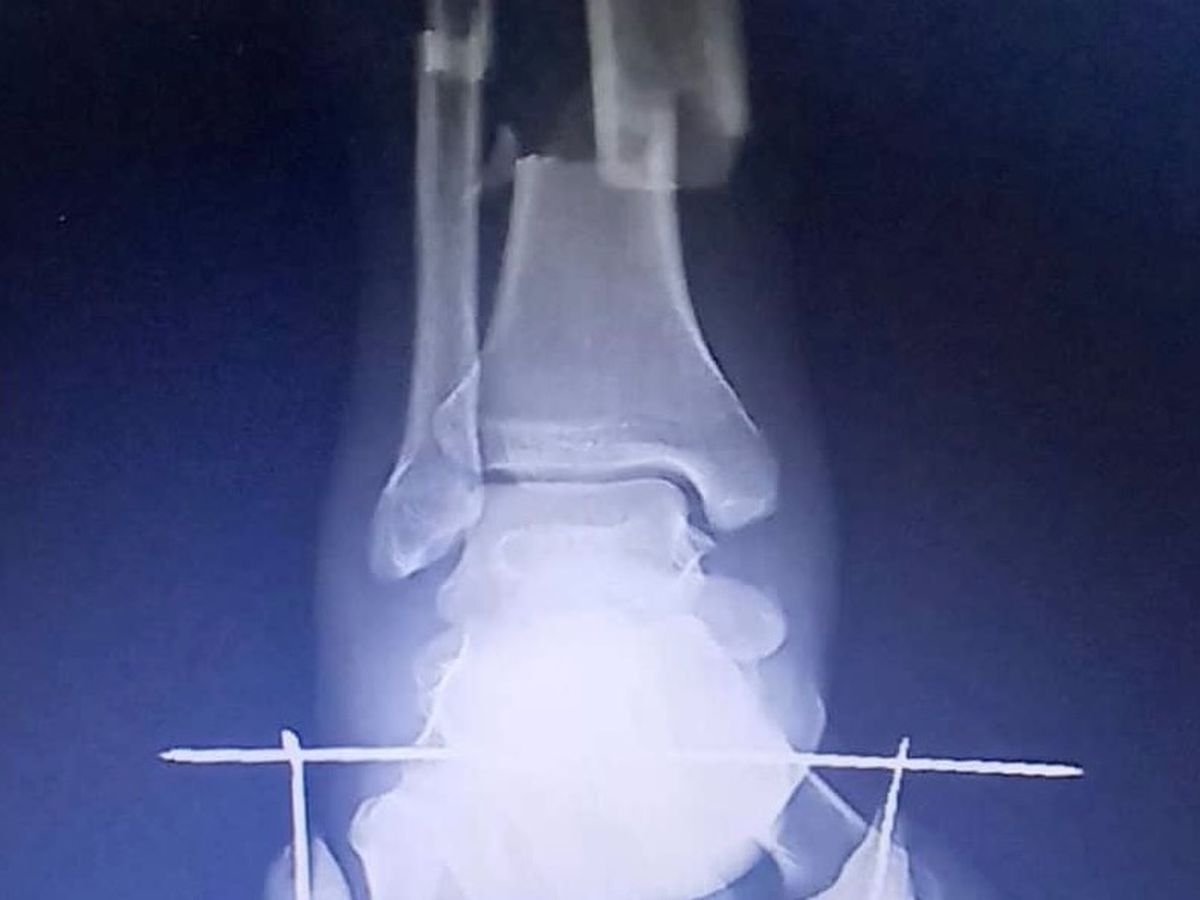

Como resultado del accidente, sufrí una fractura cerrada de tibia y peroné. Fui ingresado en un hospital público, donde me realizaron una primera cirugía y colocaron material de osteosíntesis para estabilizar mis huesos.

Hoy, sigo en un proceso de recuperación complicado. Necesito una nueva cirugía para retirar el material de osteosíntesis y reconstruir el hueso, evitando así el riesgo de osteomielitis (una grave infección ósea). Actualmente, mi diagnóstico incluye una pseudoartrosis ósea, lo que significa que el hueso no ha sanado correctamente.

As a result of the accident, I suffered a closed tibia and fibula fracture. I was admitted to a public hospital, where I underwent my first surgery, during which doctors placed osteosynthesis material to stabilize my bones.

Today, I am still facing a challenging recovery. I need a second surgery to remove the osteosynthesis material and reconstruct the bone, preventing the risk of osteomyelitis (a severe bone infection). I have also been diagnosed with bone pseudoarthrosis, meaning my bones have not healed properly.